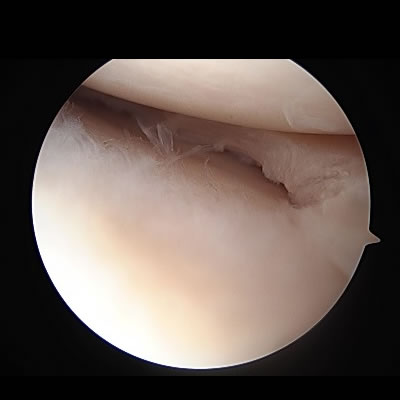

肩関節唇形成術(反復性肩関節脱臼)

関節鏡で肩関節の中を確認し、細い処置具や糸の着いたアンカーを使って、剥がれた骨や関節唇(靱帯)を元の状態に修復します。

ラグビーなどのコンタクトスポーツで大きな外力が加わることがあらかじめ予測される場合は、元の状態に戻すだけでは不十分と考え、肩関節の前方にある烏口突起という骨を肩関節に移植するBristow法といわれる処置を追加し、肩関節を補強します。